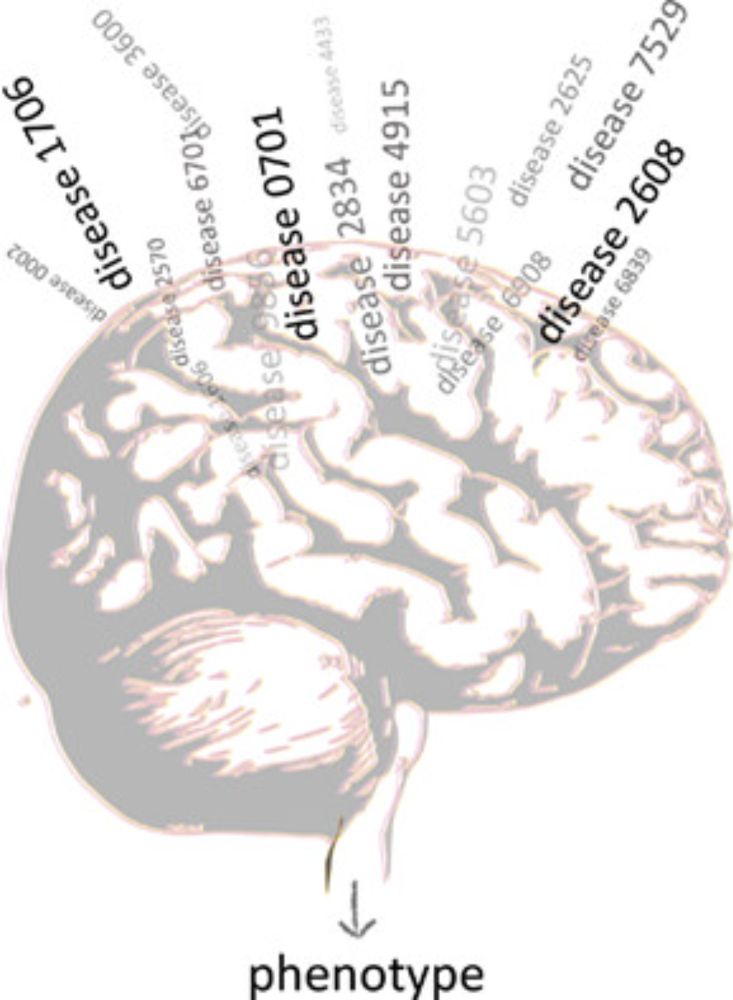

Computational Movement Disorders Lab

https://sadnickalab.org

Funded by @ wellcome.org/

doi.org/10.1002/mds....

doi.org/10.1002/mds....

doi.org/10.1002/mds....

academic.oup.com/braincomms/a...

academic.oup.com/braincomms/a...

onlinelibrary.wiley.com/share/author...

onlinelibrary.wiley.com/share/author...